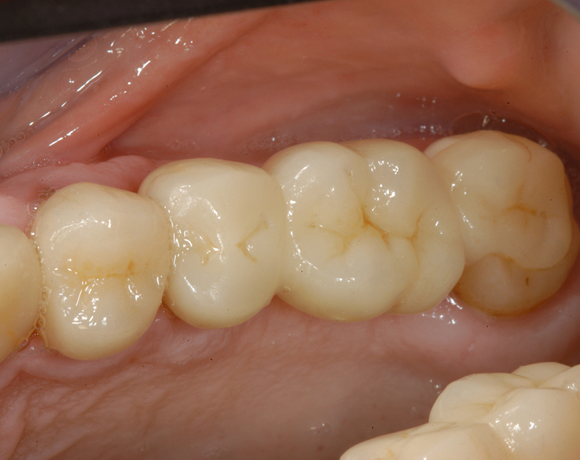

6 Implantate und viele Kronen und Brücken

Mit dem zweiteiligen vollkeramischen Implantat lassen sich auch große Lücken überbrücken.

Im vorliegenden Patientenfall waren die Zähne 11 – 26 mit einer provisorischen Brücke versorgt, der Patient konnte damit aber nicht essen. Auch im Unterkiefer waren die vorhandenen Kronen und Brücken insuffizient. Es wurde eine komplette Neuversorgung für Ober- wie Unterkiefer geplant.